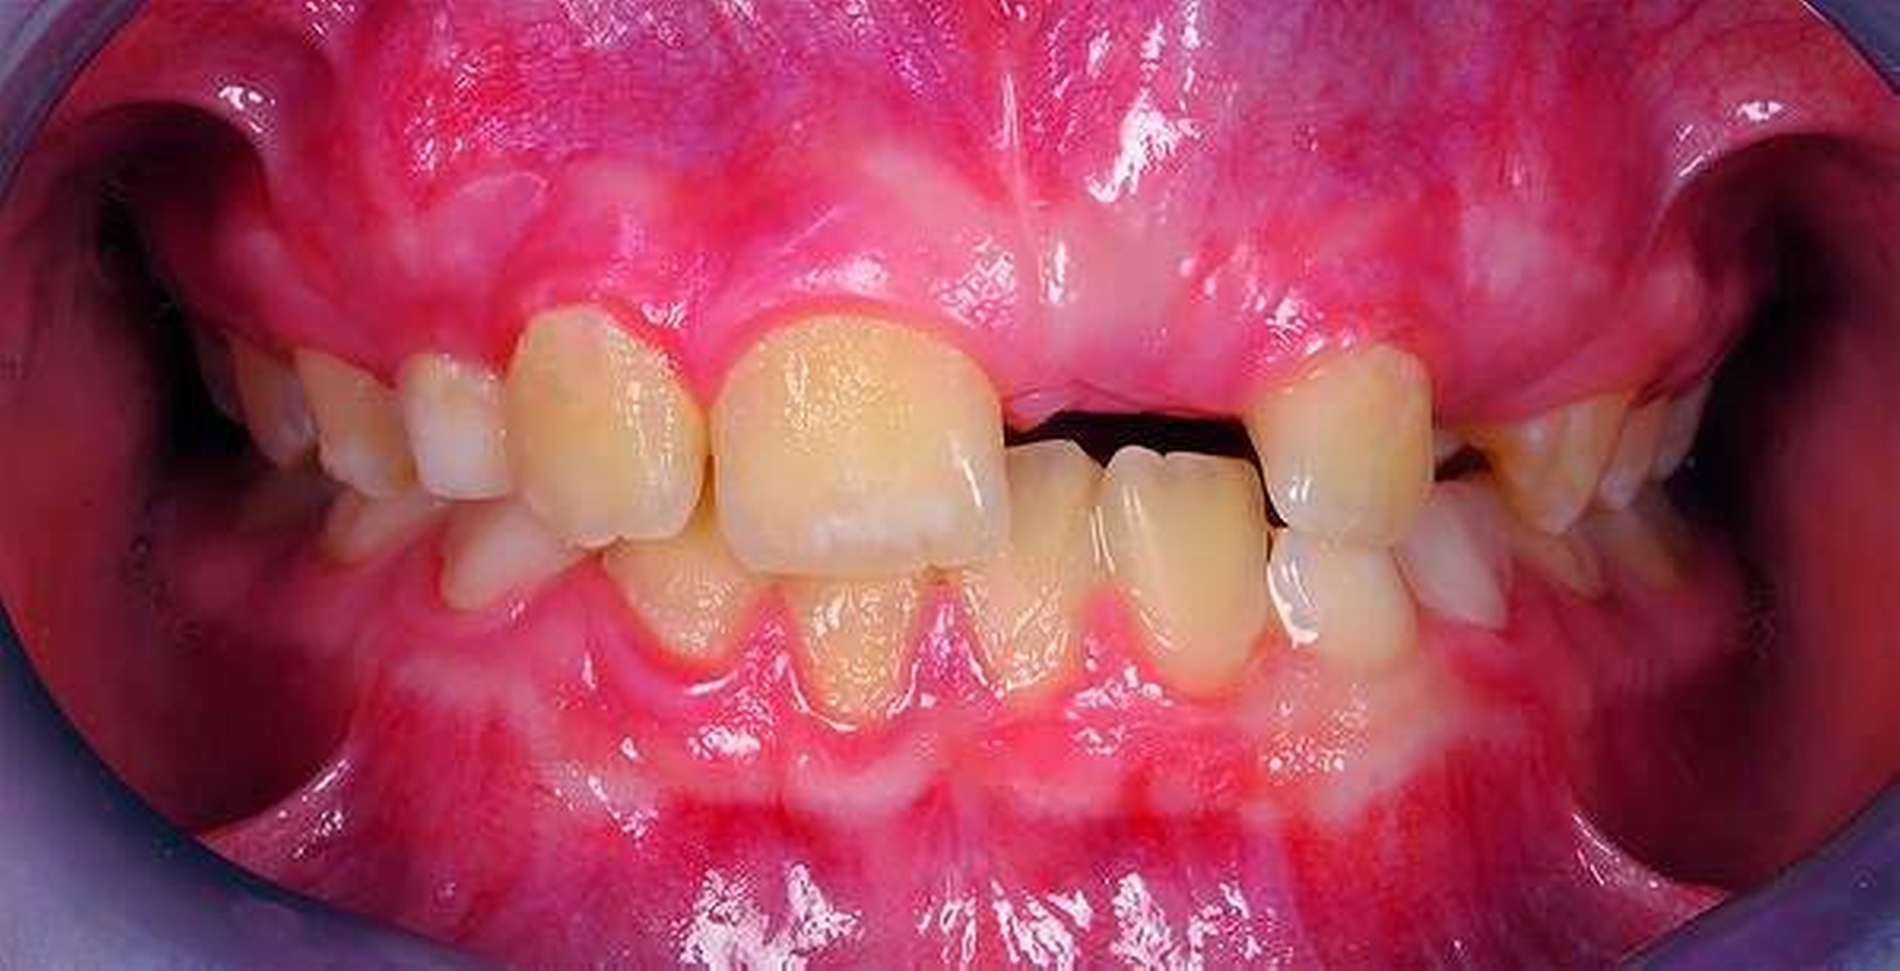

Ausgeprägte Zahnfehlstellungen und Gebissanomalien zeigen sich im reinen Milchgebiss deutlich seltener als im Wechsel- oder im permanenten Gebiss [Schopf, 2003]. Dennoch sollten bereits in dieser frühen Phase beispielsweise die Platzverhältnisse für die später durchbrechenden Zähne beurteilt werden. Im Säuglingskiefer liegen die Zahnkeime der Milch-Inzisiven zunächst in einer sagittalen Staffelstellung [van der Linden, 1980]. Die mit dem Durchbruch der Milchzähne einhergehende Bildung des Alveolarfortsatzes und die wachstumsbedingte Vergrößerung der Zahnbögen führt meist zu einer lückigen Stellung der Milchschneidezähne [Sillman, 1964] (Abbildung 1). Diese Lücken tragen dazu bei, den deutlich breiteren bleibenden Nachfolgern eine regelrechte Einordnung in den Zahnbogen zu ermöglichen [Moyers, 1976; Leighton, 1978]. Ein „schönes“, lückenloses Milchgebiss oder gar Engstände in der Front sind ein Alarmsignal im Hinblick auf spätere Platzprobleme für die bleibenden Zähne [Leighton, 1969]. Bei diesen Patienten ist eine intensive Überwachung während des Zahnwechsels der permanenten Inzisiven ratsam, um gegebenenfalls rechtzeitig Platz schaffende Maßnahmen einleiten zu können.